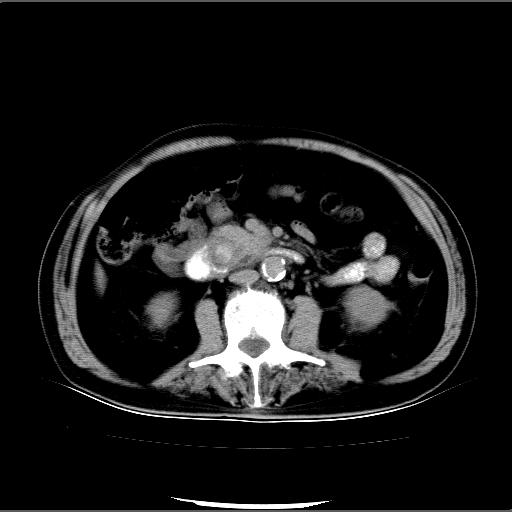

患者男82岁,黄染,发热10天,无腹痛。

1胆总管下端结石伴肝内外胆管扩张;2胆囊颈部结石伴胆囊积液

胆囊多发结石,胆囊积液;胆总管中下段结石,中上段扩张。

胆总管下段结石伴胆道系统扩张;胆囊炎伴胆囊结石.

1、胆总管壶腹部结石并胆总管、胆囊及肝内胆管扩张。2、胆囊多发结石。3、两下胸膜局限性增厚。4、胃体部大弯侧胃壁稍厚,建议:多量饮水后增强ct扫描除外占位性病变。

十二指肠乳头旁憩室伴胆总管下段结石,胆囊结石

此病例有结果了:患者术后为:胆总管下段结石伴胆道系统扩张;胆囊炎伴胆囊结石。

各位战友分析的都很正确,是一个典型的病例。